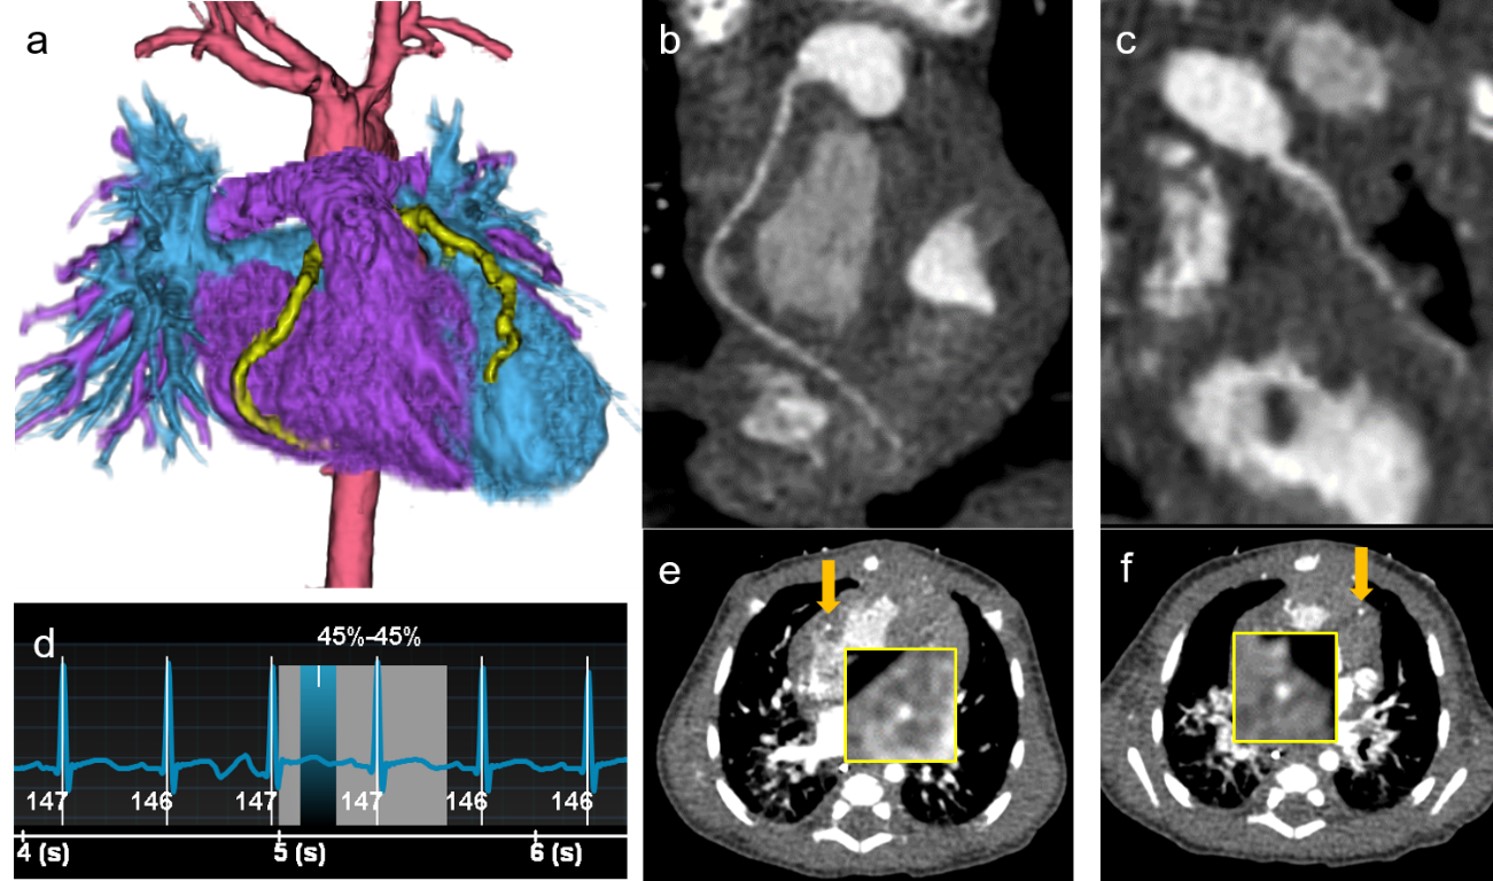

Fig.5に生後28日, 完全大血管転位症のジャテン手術後の症例を提示する。本症例は術後の心血管の形態評価および移植冠動脈の走行確認目的で心臓CT施行された。

撮影時の心拍数は147bpmであるが, 0.23sec/rotで1心拍を心電図同期撮影することで, 3D画像やCurved Planar Reconstruction (CPR)において, 移植冠動脈の走行が末梢まで確認可能であった。また前述した撮影時の工夫によって, 1心拍撮影でもCTDIvolが1.38mGy, 画像ノイズに関してはスライス厚0.625mmでStandard deviation (SD)がおよそ20であり, 低被ばくで画質を担保できている。

RevolutionApexElite_Shimane06.jpg

Fig.5 生後28日, 完全大血管転位症のジャテン手術後の症例

(a)心血管および移植冠動脈の3D画像 (b)右冠動脈CPR (c)左冠動脈CPR

(d)撮影時の心電図波形 (e)右冠動脈のAxial画像 (f)左冠動脈のAxial画像